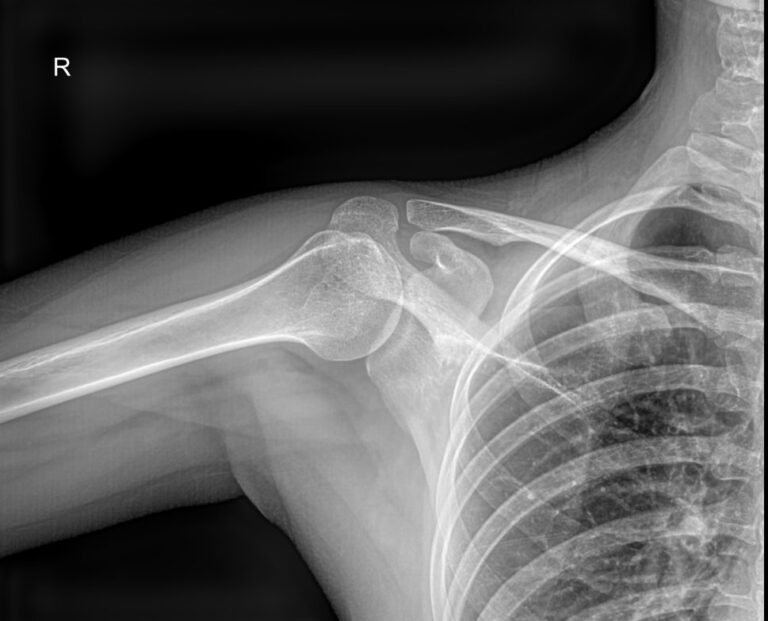

Плечевая кость ― одна из самых крепких в организме, что для ее повреждения требуется удар значительной силы. Переломы могут сопровождаться вывихами плечевого и локтевого суставов. Давно залеченная травма при неблагоприятных обстоятельствах может вызвать прерождение костной ткани.

Во всех случаях первичным методом диагностики будет рентгенография. Это простая и информативная процедура, которая не добавляет неприятных ощущений и быстро показывает полную картину патологии. Современное оборудование, которое используется в клинике «Доступная медицина», позволяет делать несколько снимков в течение короткого времени без опасности чрезмерного облучения.

Что покажет рентген плечевой кости

• Травматические повреждения, в том числе зажившие;

• Формирование костной мозоли;

• Патологические изменения костной ткани: разрежение, некроз, деструкция и другие;

• Состояние смежных суставов, вошедших в снимок;

• Опухоли и метастазы.